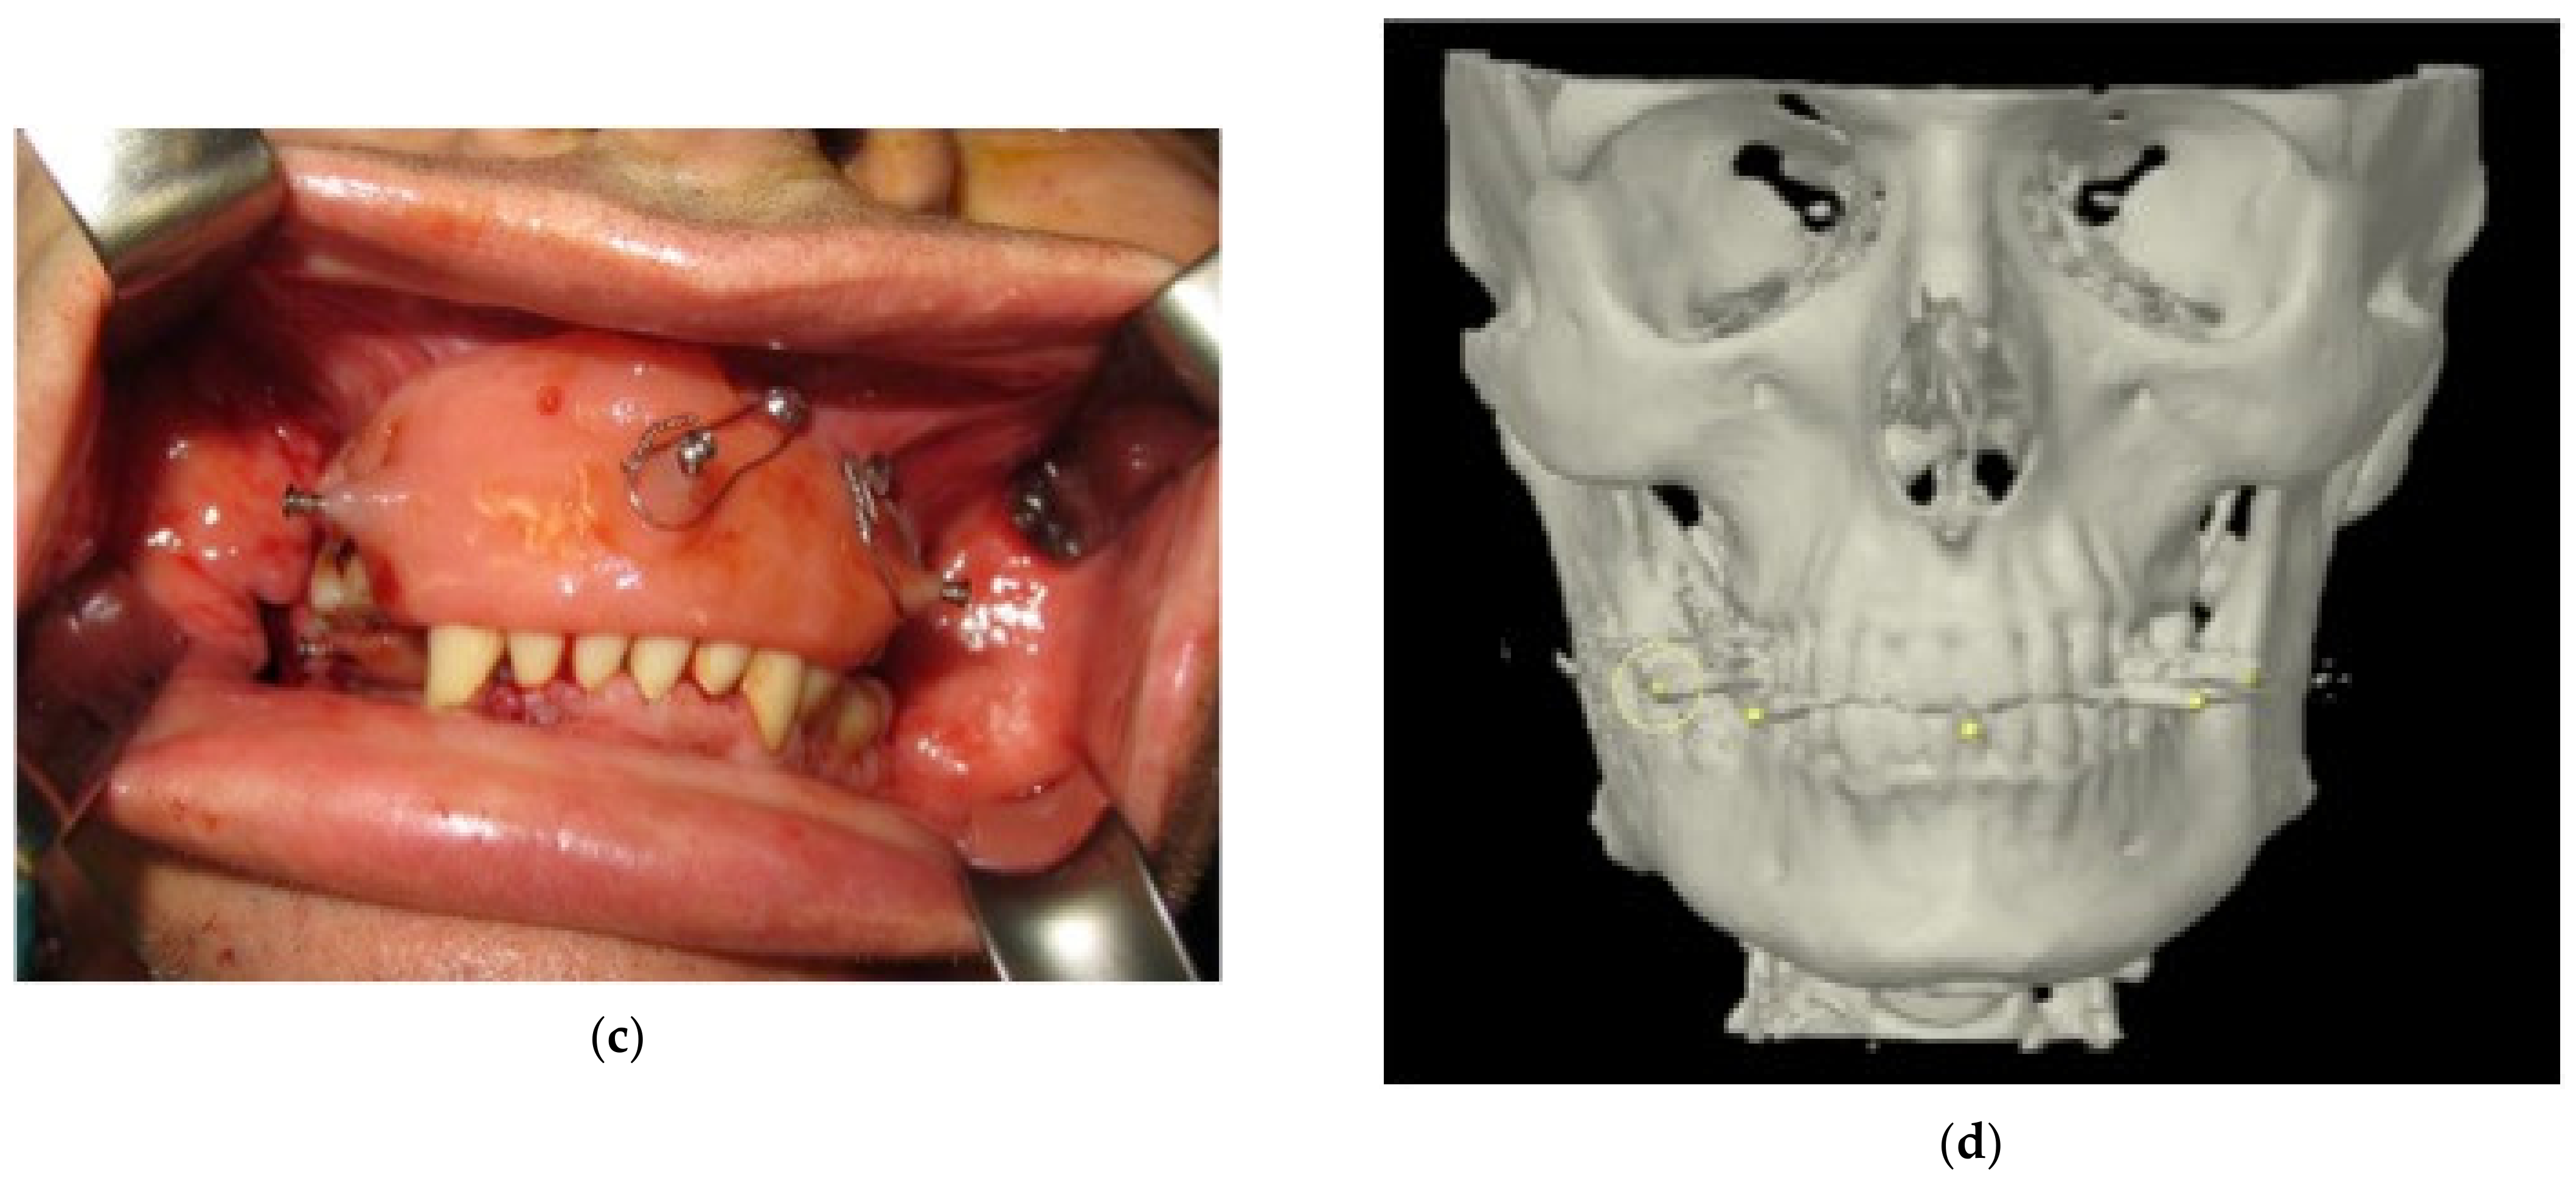

2.5. Intra-Operative Surgical Navigation

2.6. Post-Operative Evaluation